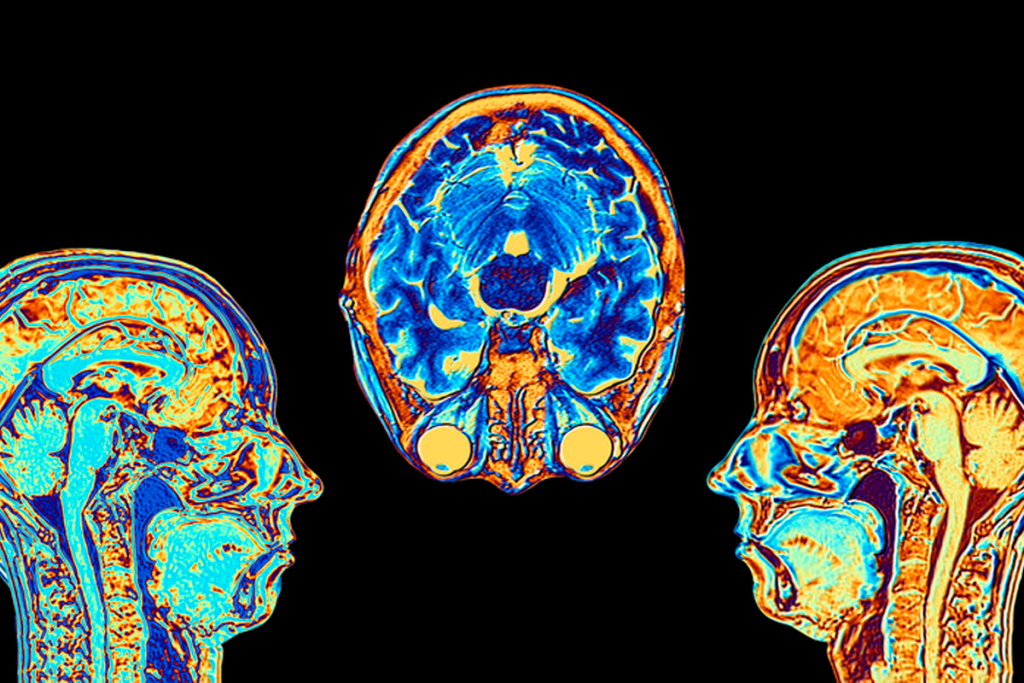

Interpreting SPECT Brain Images

Understanding SPECT images takes knowledge of brain anatomy and function. Experts compare the tracer’s spread in the brain. This helps spot where blood flow or activity might be off.

By looking at tracer patterns, doctors can find signs of anxiety disorders. This helps in diagnosing and planning treatments.

Only experts can accurately read SPECT images. They know the difference between normal and abnormal brain patterns. Their skill is key to reliable SPECT results in medical practice.